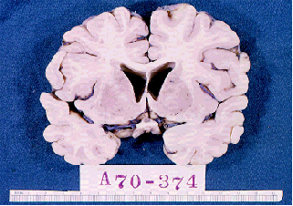

How many lay people in the 21st century know that our brain contains chambers, called ventricles, which are filled with cerebrospinal fluid? Shakespeare did 400 years ago. In Love’s Labor’s Lost Holofernes says (Act IV, scene 2, line 66): “These are begot in the ventricle of memory…”